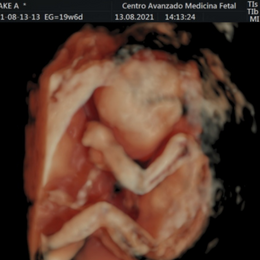

Ecografía del corazón fetal en 4D

- Las formas nuevas de ecografía pueden proporcionar imágenes en 5-D.